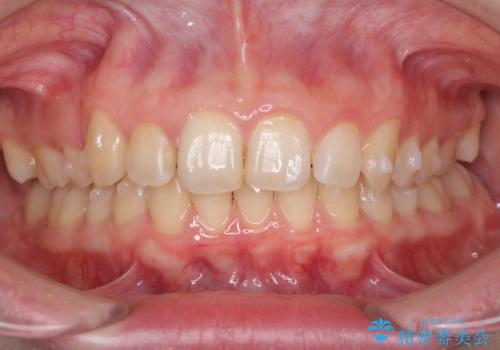

- 八重歯を気にして来院された患者様です。

八重歯の後ろの歯を1歯抜歯し、補助装置(リンガルアーチ)を用いて八重歯の位置を改善し、その後インビザラインにより矯正治療を行うこととしました。

下顎前歯が1本欠損したスリーインサイザーという状態であるため、上下の前歯の咬み込みが深くなったり、奥歯の咬み合わせが理想的なものとならなかったりという仕上がりになってしまいます。

前歯の見た目や奥歯の咬み合わせに、患者様が違和感を感じない状態として治療を終えました。